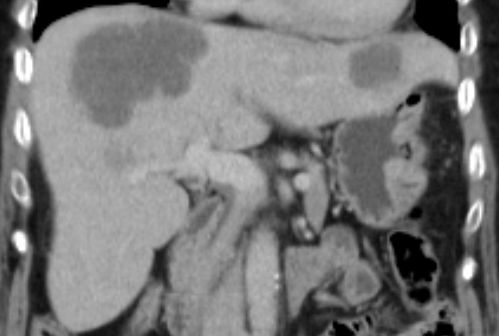

| Leber | 66jährige Frau nach Gastektomie: Lebermetastasen.![]() |